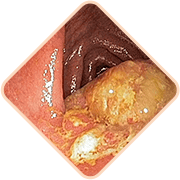

- Vratite tonus i elastičnost vena zahvaljujući ekstraktu stolisnika, ekstraktu palmetto pile

- Započnite regeneraciju tkiva anusa zahvaljujući ekstraktu palme sabal, kore hrasta, aloe

- Uklonite infekcije i gnojne procese zahvaljujući kamilici, krumpiru i poštenju

- Sprječava povratak hemoroida zahvaljujući celandinu